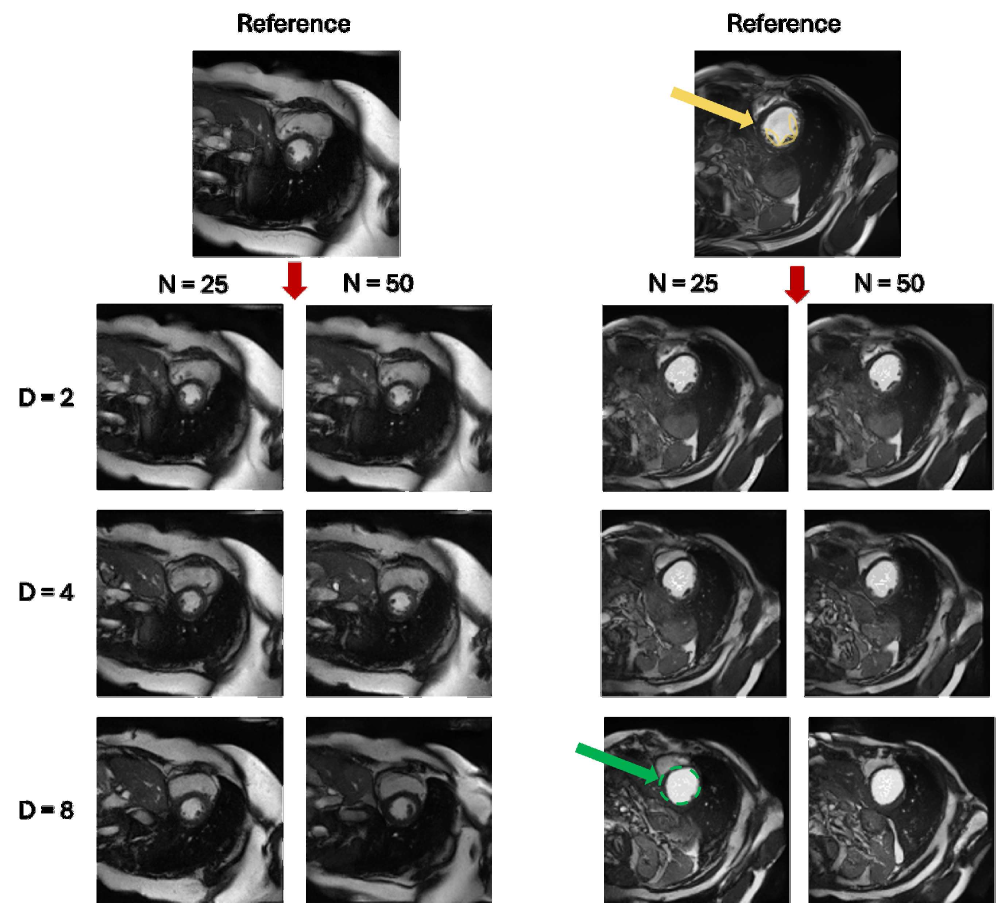

Refer to caption

Figure 3: Image synthesis using various scaling factor DD and diffusion range NN with fixed τ=6\tau=6. As DD increases, more semantic information lost (yellow \rightarrow green region).